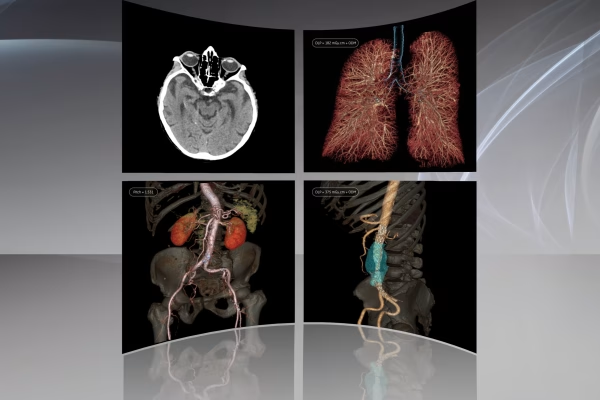

Notre service d’Imagerie Médicale et Radiologie Interventionnelle, un pilier essentiel de notre approche diagnostique. Avec une expertise avancée et une technologie de pointe, nous offrons une imagerie de haute précision pour éclairer votre parcours médical. Notre équipe de spécialistes dévoués s’engage à fournir des diagnostics fiables et des soins personnalisés, en mettant l’accent sur votre bien-être et votre satisfaction. Vous pouvez compter sur nous pour une expérience professionnelle et des résultats médicaux de qualité supérieure.

IRM GE Signa Explorer 1.5T

Scanner GE Optima CT520